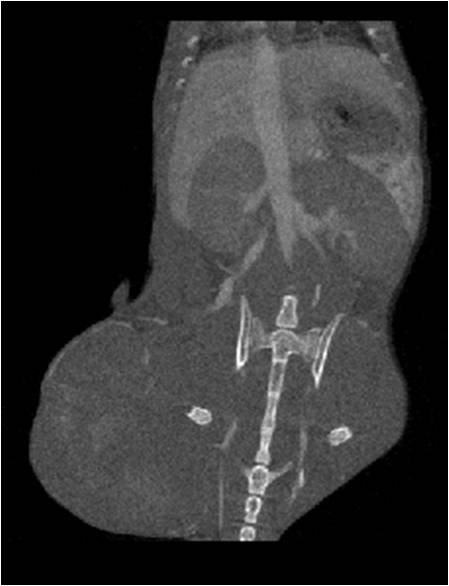

心血管

胸部和心血管的層析成像 胸部和心血管的3D圖像